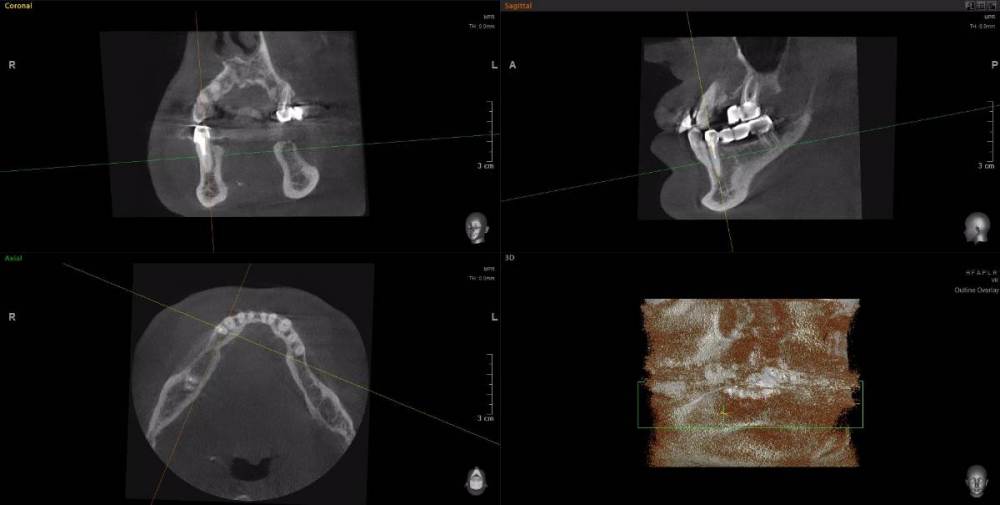

Dude Опубликовано 1 апреля, 2021 Поделиться Опубликовано 1 апреля, 2021 По плану в 1 этапе, кроме остального: лечение каналов и укрепление их стекловолоконными штифтами: 16, 25, 27, 44, 47; имплантация 14, 15, 17, 12, 11, 21, 22, 24, 26, 36, 37, 46, 45. Во 2 этапе (через 5-6 месяцев) установка коронок. Лечение в другой стране. Чтобы сократить длительность первого этапа, предложили лечение зубов сделать на 2 этапе. Очень засомневался, можно делать имплантацию с невылеченными зубами? Ссылка на комментарий

Dude Опубликовано 1 апреля, 2021 Автор Поделиться Опубликовано 1 апреля, 2021 https://disk.yandex.ru/d/6d0pmZ1zArn1Og Так? Ссылка на комментарий